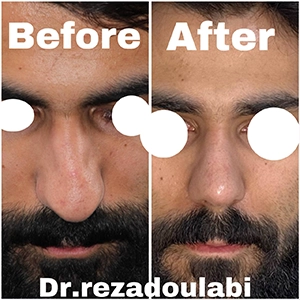

تمرکز بر نتایج «طبیعی و متناسب با صورت» بهجای تغییرات افراطی.

اصلاح افتادگی یا پهنی نوک بینی، باریکسازی متعادل

تقارن پرههای بینی و بهبود زاویه بینی و لب بالا

🎯 انتخاب بهترین جراح بینی در تهران

اگر به دنبال بهترین جراح بینی در تهران هستید، تجربه، نمونه کارهای موفق، ارتباط حرفهای با بیمار و آشنایی با تکنیکهای مدرن جراحی، معیارهایی مهم برای انتخاب شما هستند. حتماً عکسهای قبل و بعد عمل بینی بیماران را ببینید و در جلسه مشاوره تمام انتظارات خود را مطرح کنید.

👨⚕️ درباره دکتر سید رضا سید محمد دولابی

دکتر سید رضا سید محمد دولابی، جراح و فوقتخصص گوش، حلق، بینی و جراحی سر و گردن، از برترین پزشکان کشور در زمینه جراحی زیبایی و درمانی بینی و سینوس بهشمار میرود. ایشان فلوشیپ فوق تخصصی خود را در تهران و فرانکفورت با بالاترین رتبه علمی دریافت کرده و موفق به گذراندن امتحان بینالمللی USMLE نیز شدهاند.